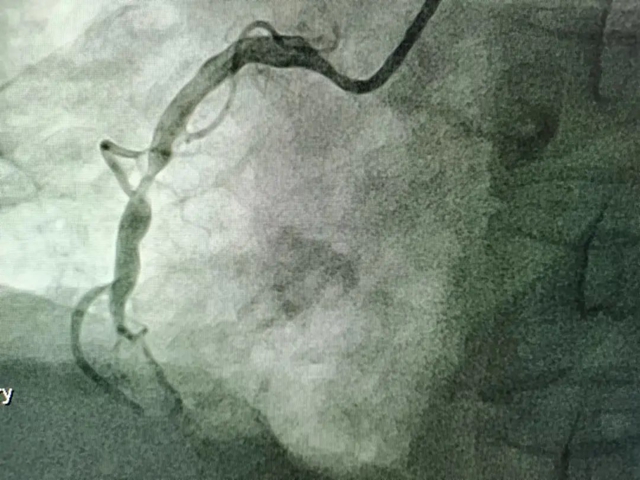

经医生接诊后为匡阿姨完善了相关检查,终于找到了病因:匡阿姨冠状动脉病变严重,存在心肌梗死,冠状动脉造影提示右冠脉内大量血栓,前降支重度狭窄。

右冠脉术前造影